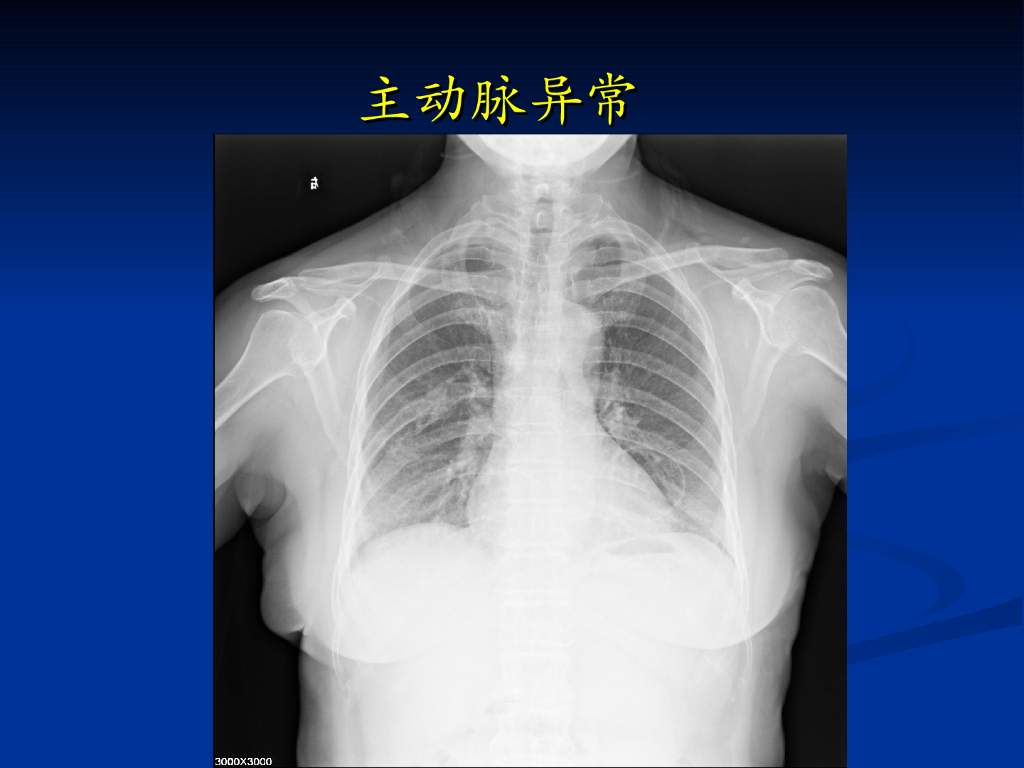

《放射诊断学》循环系统异常影像学表现.pdf